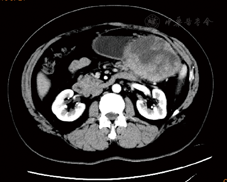

术后仁济医院放疗23次,放疗剂量46 Gy分23次。定期我院随访,2018年4月18日复查CA125为48.54 U/ml,略高于正常;8月15日复查CA125为24.65 U/ml。2019年6月自觉左上腹隐痛,于6月27日行腹部增强MRI,提示胃、胰尾及脾间隙内见一大小约103.5 mm×78.0 mm软组织占位,间皮瘤可能,横结肠系膜、大网膜多发小节结影,种植改变?腹膜后淋巴结增大(图1,图2,图3)。